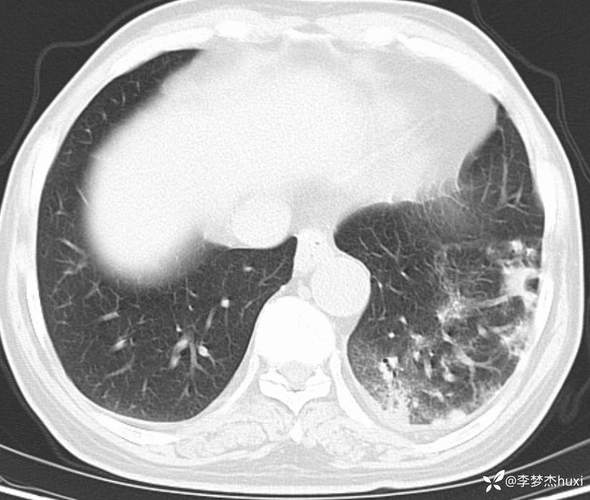

(图片来源网络,侵删)